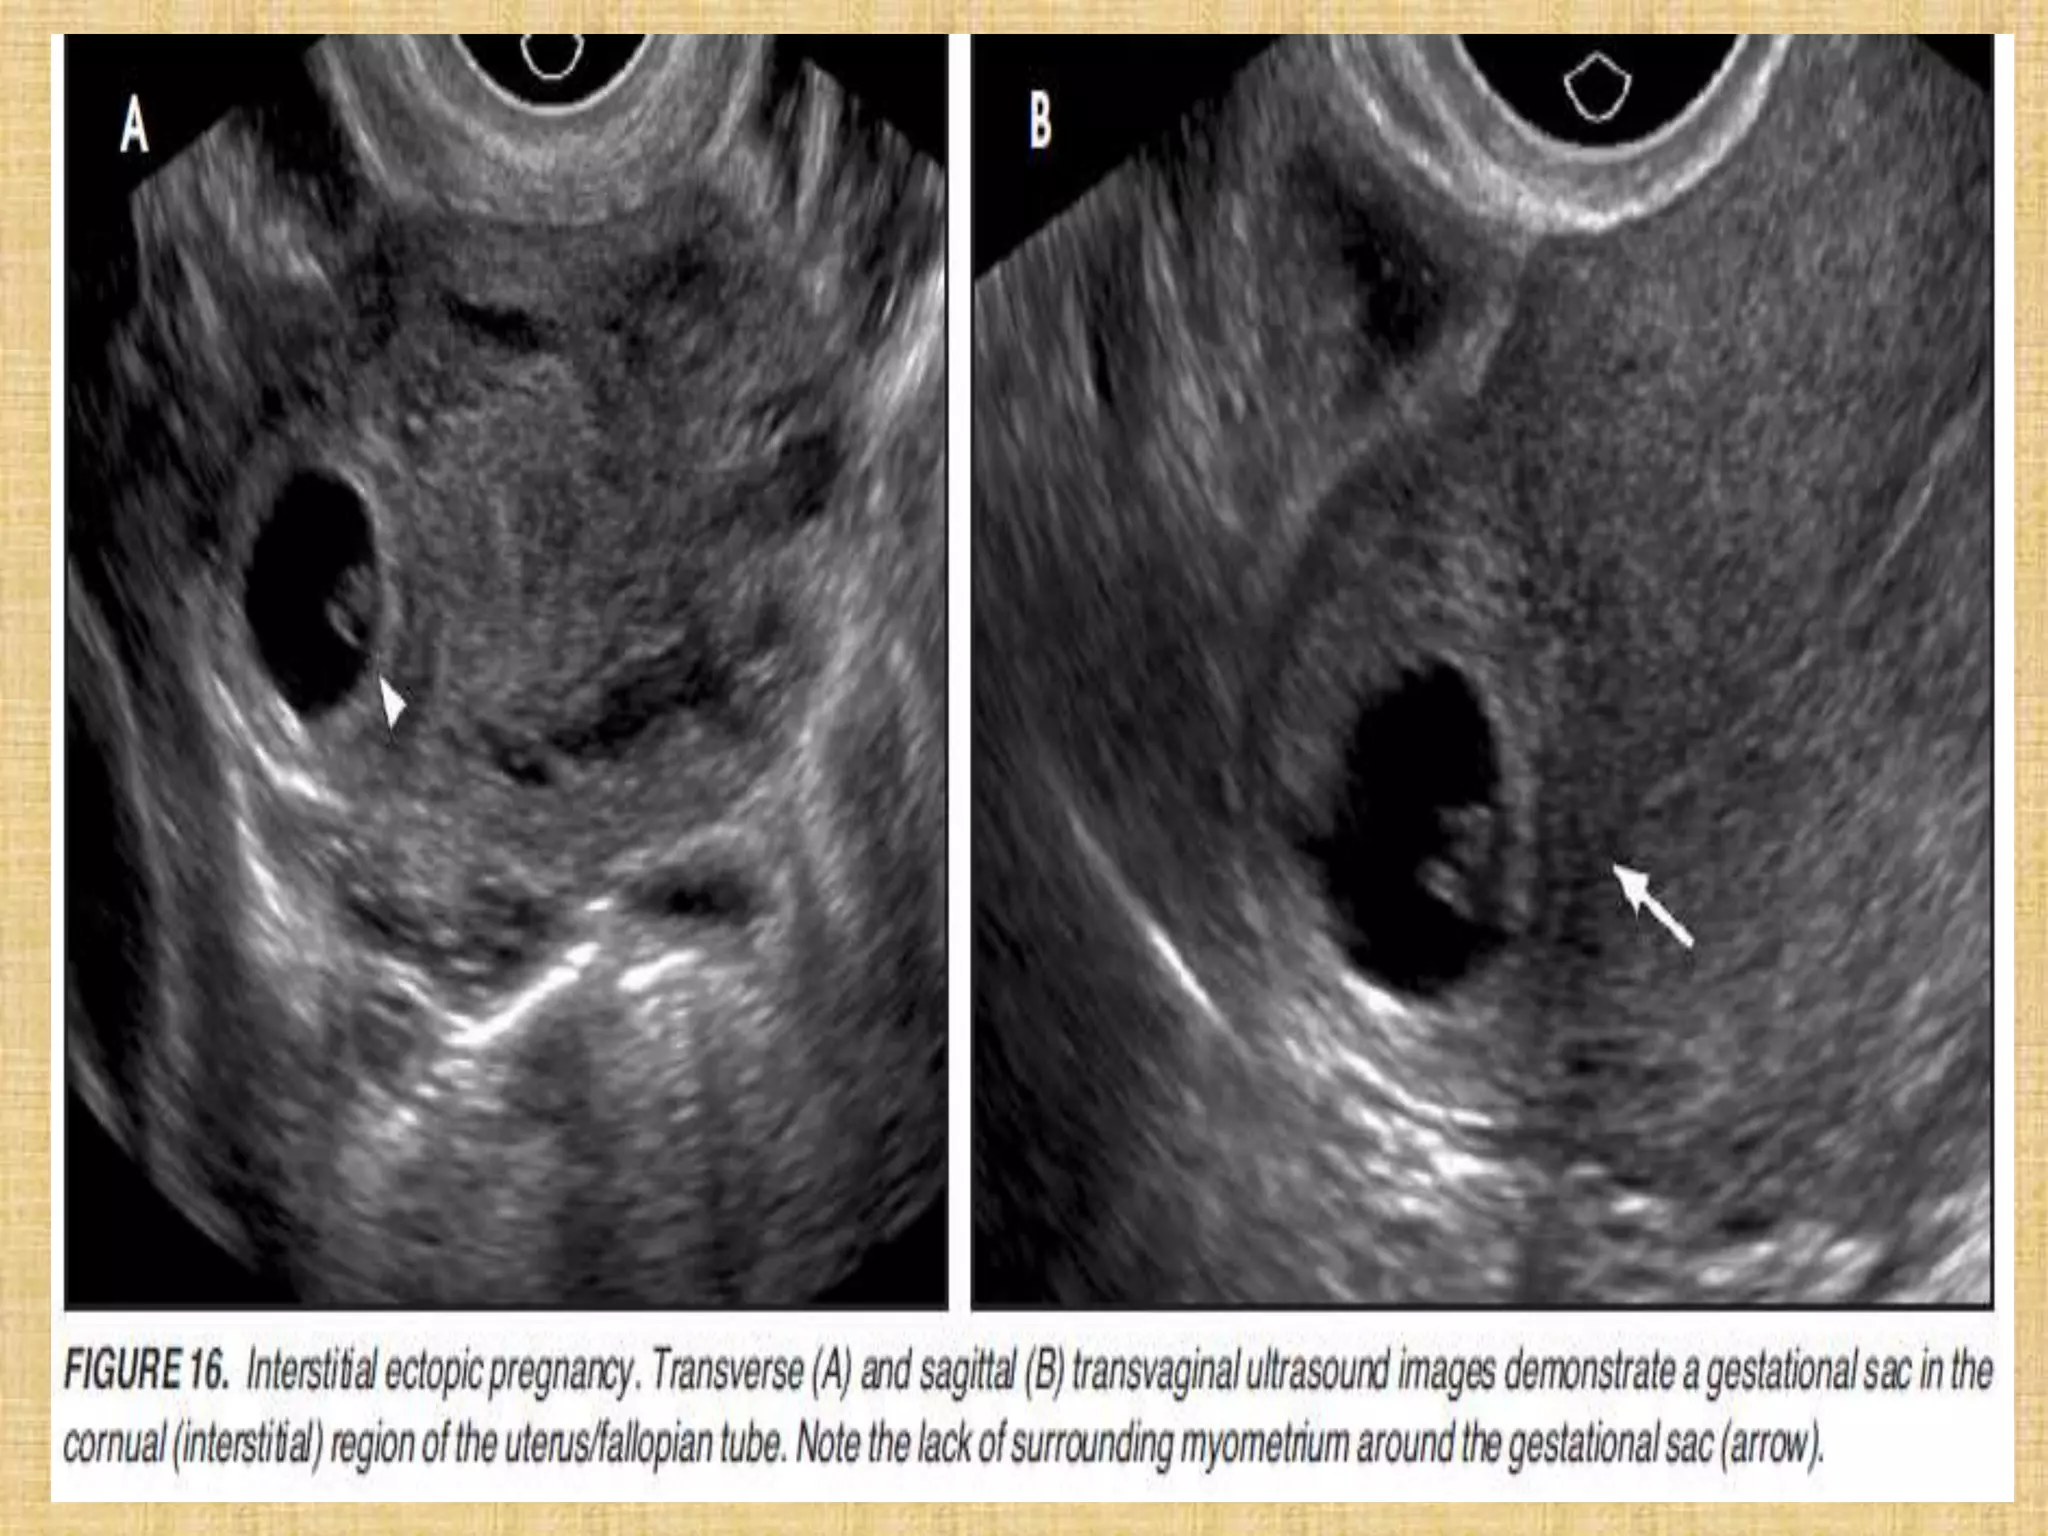

Interstitial ectopic pregnancy 8 weeks after LMP. Sagittal transvaginal view

of the uterus (UT) demonstrates a thick-walled mass arising from the

interstitial portion of the uterus. The embryo is measured with calipers.

Interstitial ectopic pregnancy8 weeks after LMP. Sagittal transvaginal view of the uterus (UT) demonstrates a thick-walled mass arising from the interstitial portion of the uterus. The embryo is measured with calipers.